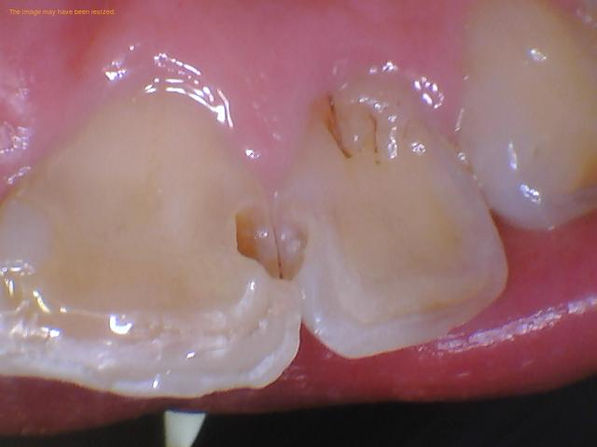

Procedure Step by Step with Photos

Signs that you may need a dental filling

Recurrent decay underneath fillings